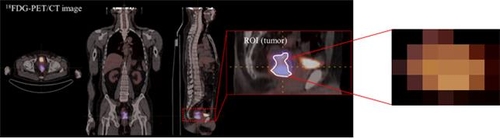

이에 연구팀은 국소 진행성 직장암 환자 156명을 대상으로 양전자방출단층촬영(PET) 영상 데이터를 학습한 AI 모델을 개발했다.

이를 이용해 수술 전 항암 방사선 치료 후 완전관해를 예측한 결과 예측 정확도는 76%로 나타났다.

여기에 부천순천향병원 환자의 영상 데이터와 치료 결과를 학습시키자 예측 정확도가 87.5%로 올랐다고 연구팀은 설명했다.